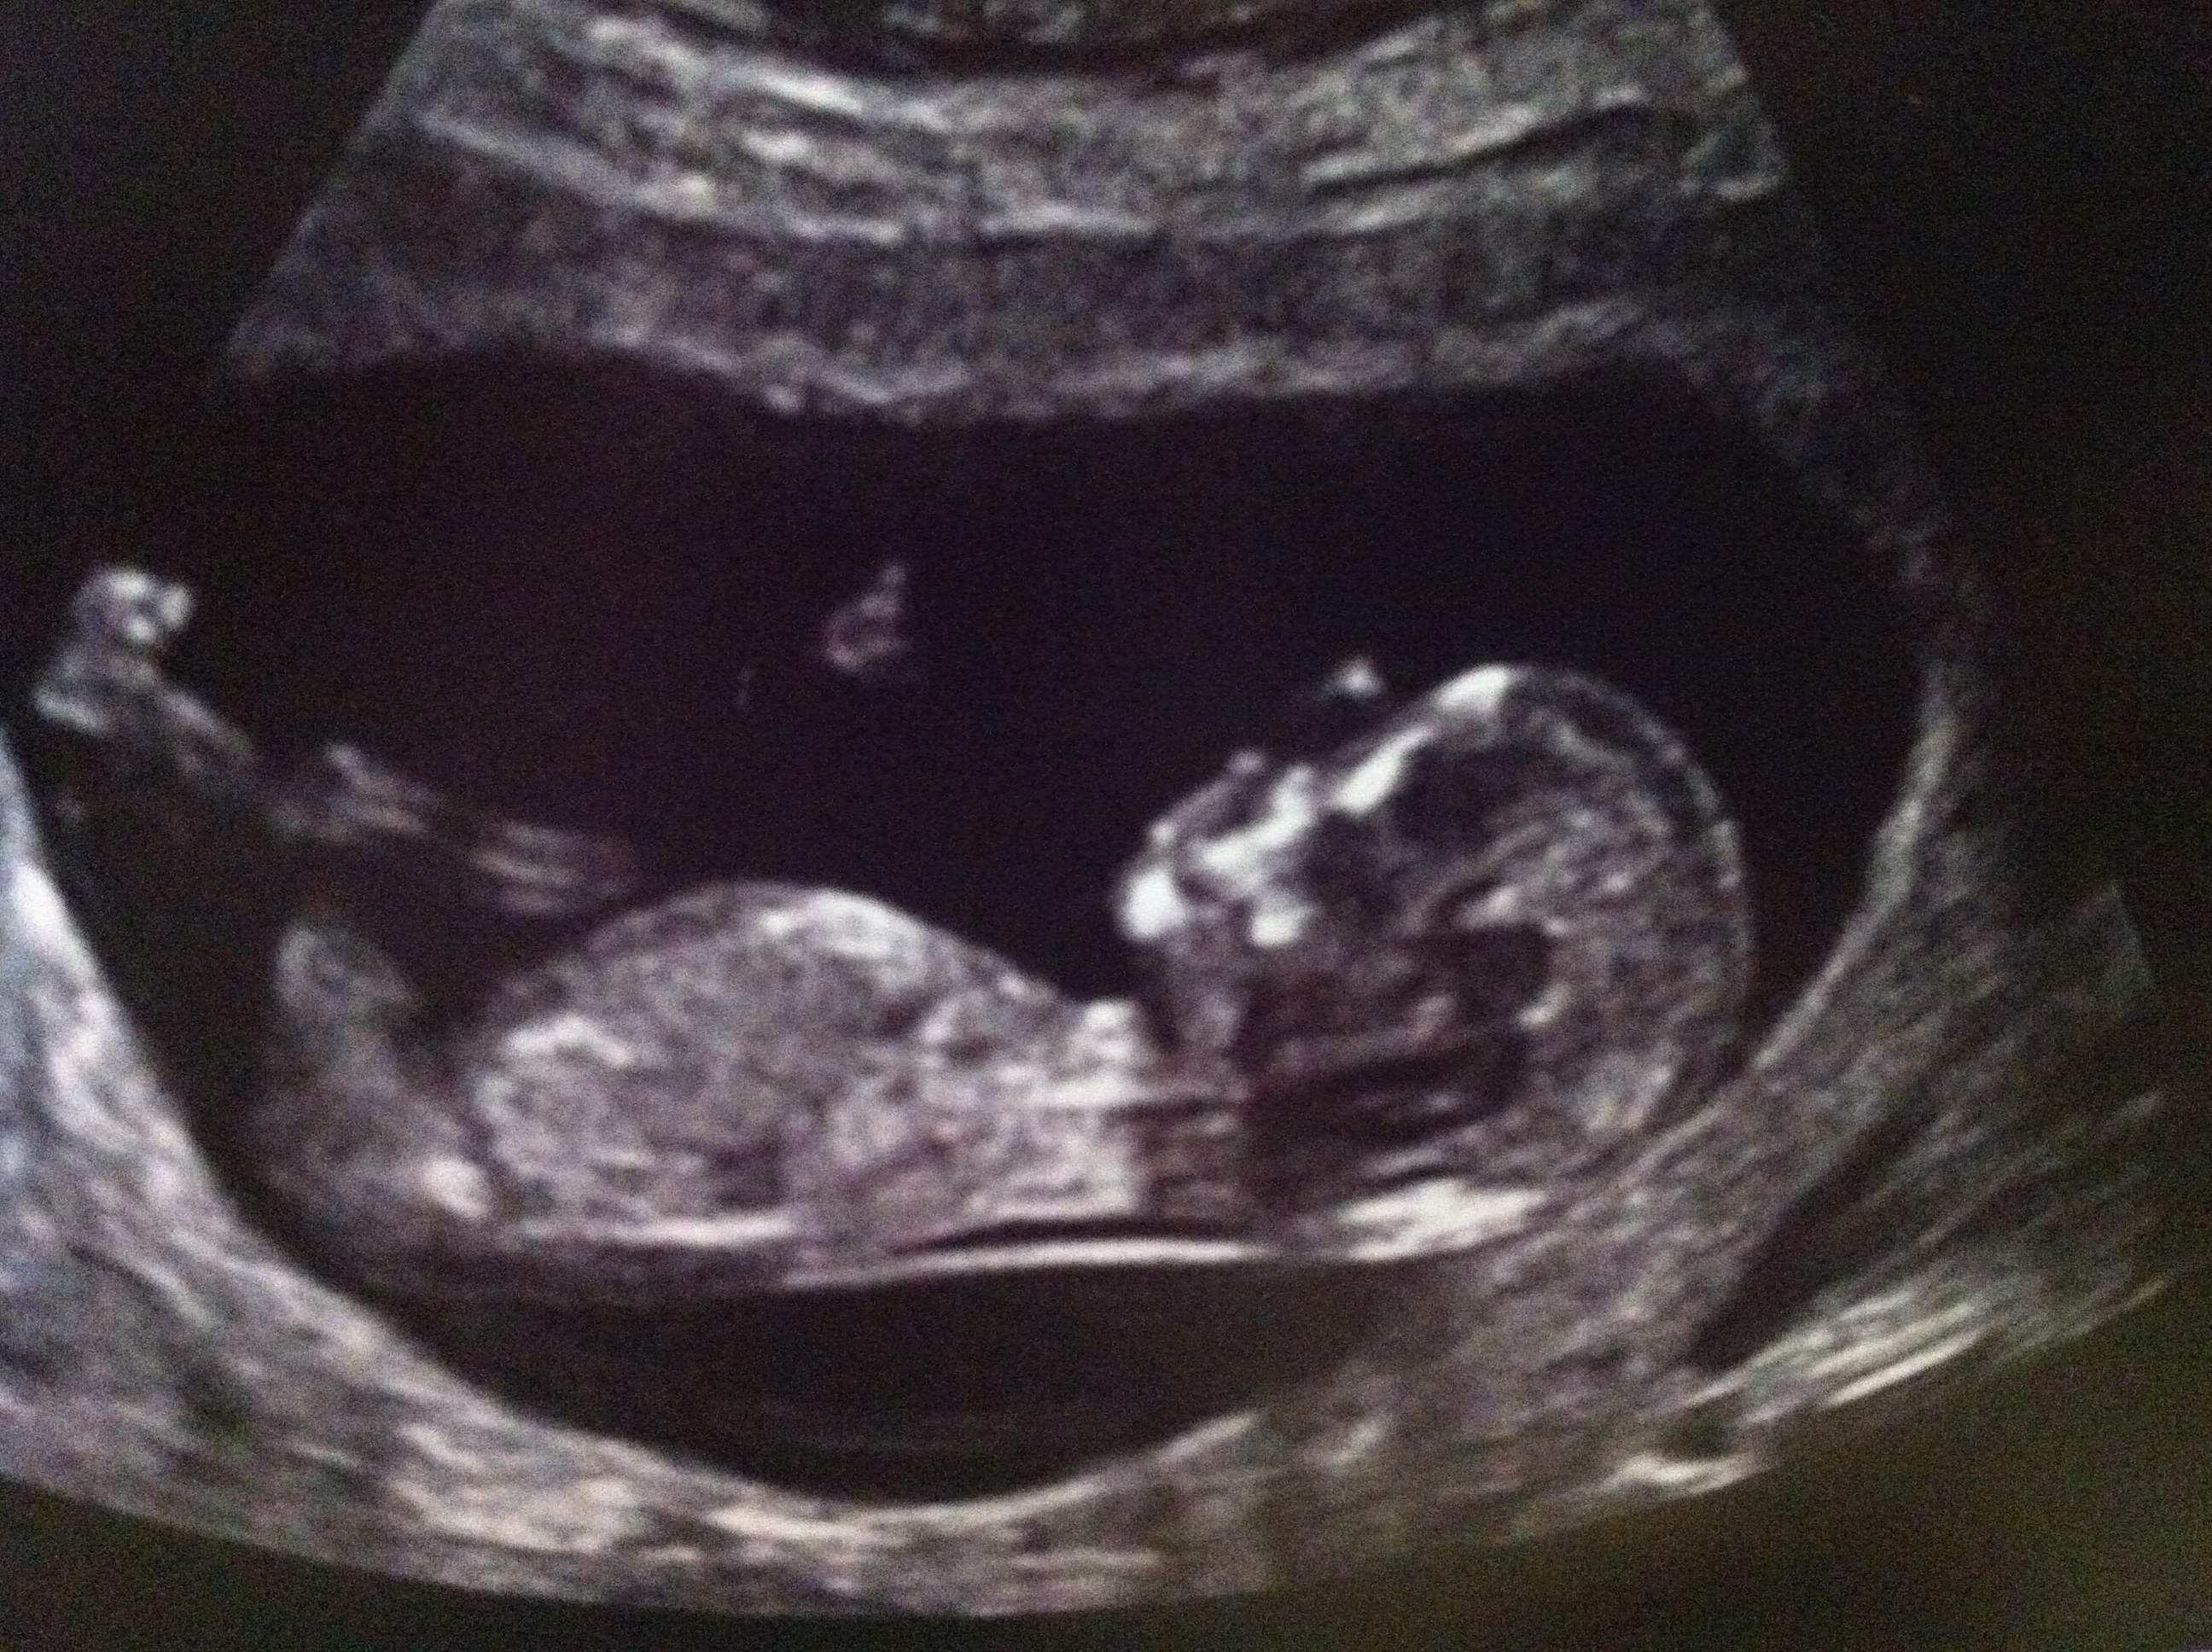

UPDATE 20 weeks photo added

Here is my scan at 12w 4d but baby measured at 13w 1d baby would not sit still so couldnt get a clear shot i went through ultrasound and this is what i found would love to hear what you think thanks guys